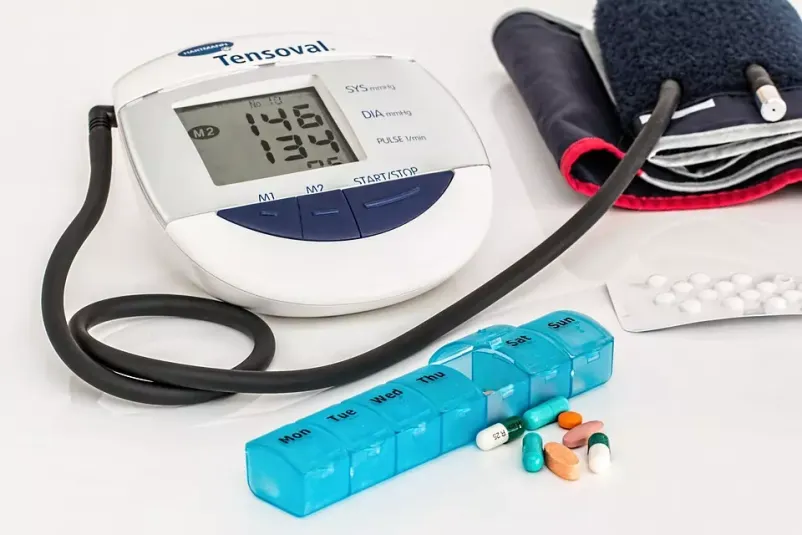

Osnovna orientacija naše dejavnosti je zgodnje odkrivanje srčnožilnih bolezni, poleg te dejavnosti pa smo usmerjeni predvsem v celovito in integralno internistično obravnavo, ki zajema: